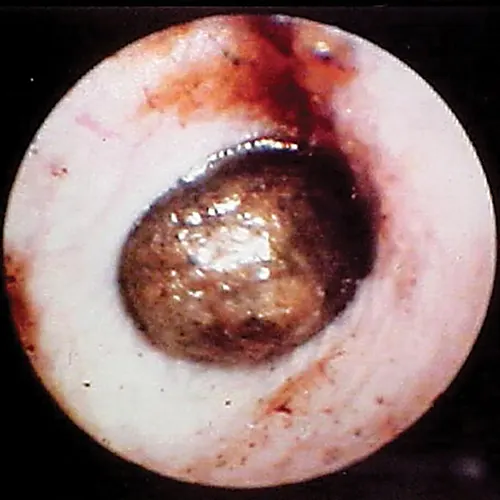

Globoid brown-to-black mass occluding internal ear canal.

FIGURE 14

Wax plug (ceruminolith) on the eardrum

Wax plug in an ear. Accumulations of wax (cerumenolith) commonly  show up at the eardrum when the eardrum epithelial surface has been previously compromised.  Dried oily medication and inspissated mucus from the bulla can look similar.

Cerumen accumulation against the eardrum, in addition to stenosis and hyperplasia, can impede conduction of sound waves and result in temporary hearing loss. Ceruminoliths require mechanic removal, preferably with endoscopic grasping forceps through a video otoscope with the patient anesthetized. If the eardrum is not intact, exudates such as mucus and pus can leak into the horizontal canal and inspissate at the eardrum. This condition can look like a ceruminolith. The mucoid secretions dissolve in water and can be removed with a water or saline flush of the horizontal canal.